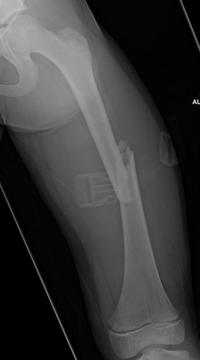

Fracture du fémur – ECMES 9 février 2024 par Damien Fracture diaphysaire du fémur G Fracture diaphysaire du fémur G : radiographie de FaceOn note un chevauchement et un déplacement en varus Fracture diaphysaire du fémur G Fracture diaphysaire du fémur G après Embrochage Centro-médullaire Elestique Stable. Radiographie post-opératoire de Face Fracture diaphysaire du fémur G Fracture diaphysaire du fémur G après Embrochage Centro-médullaire Elestique Stable. Radiographie de Face à 6 mois